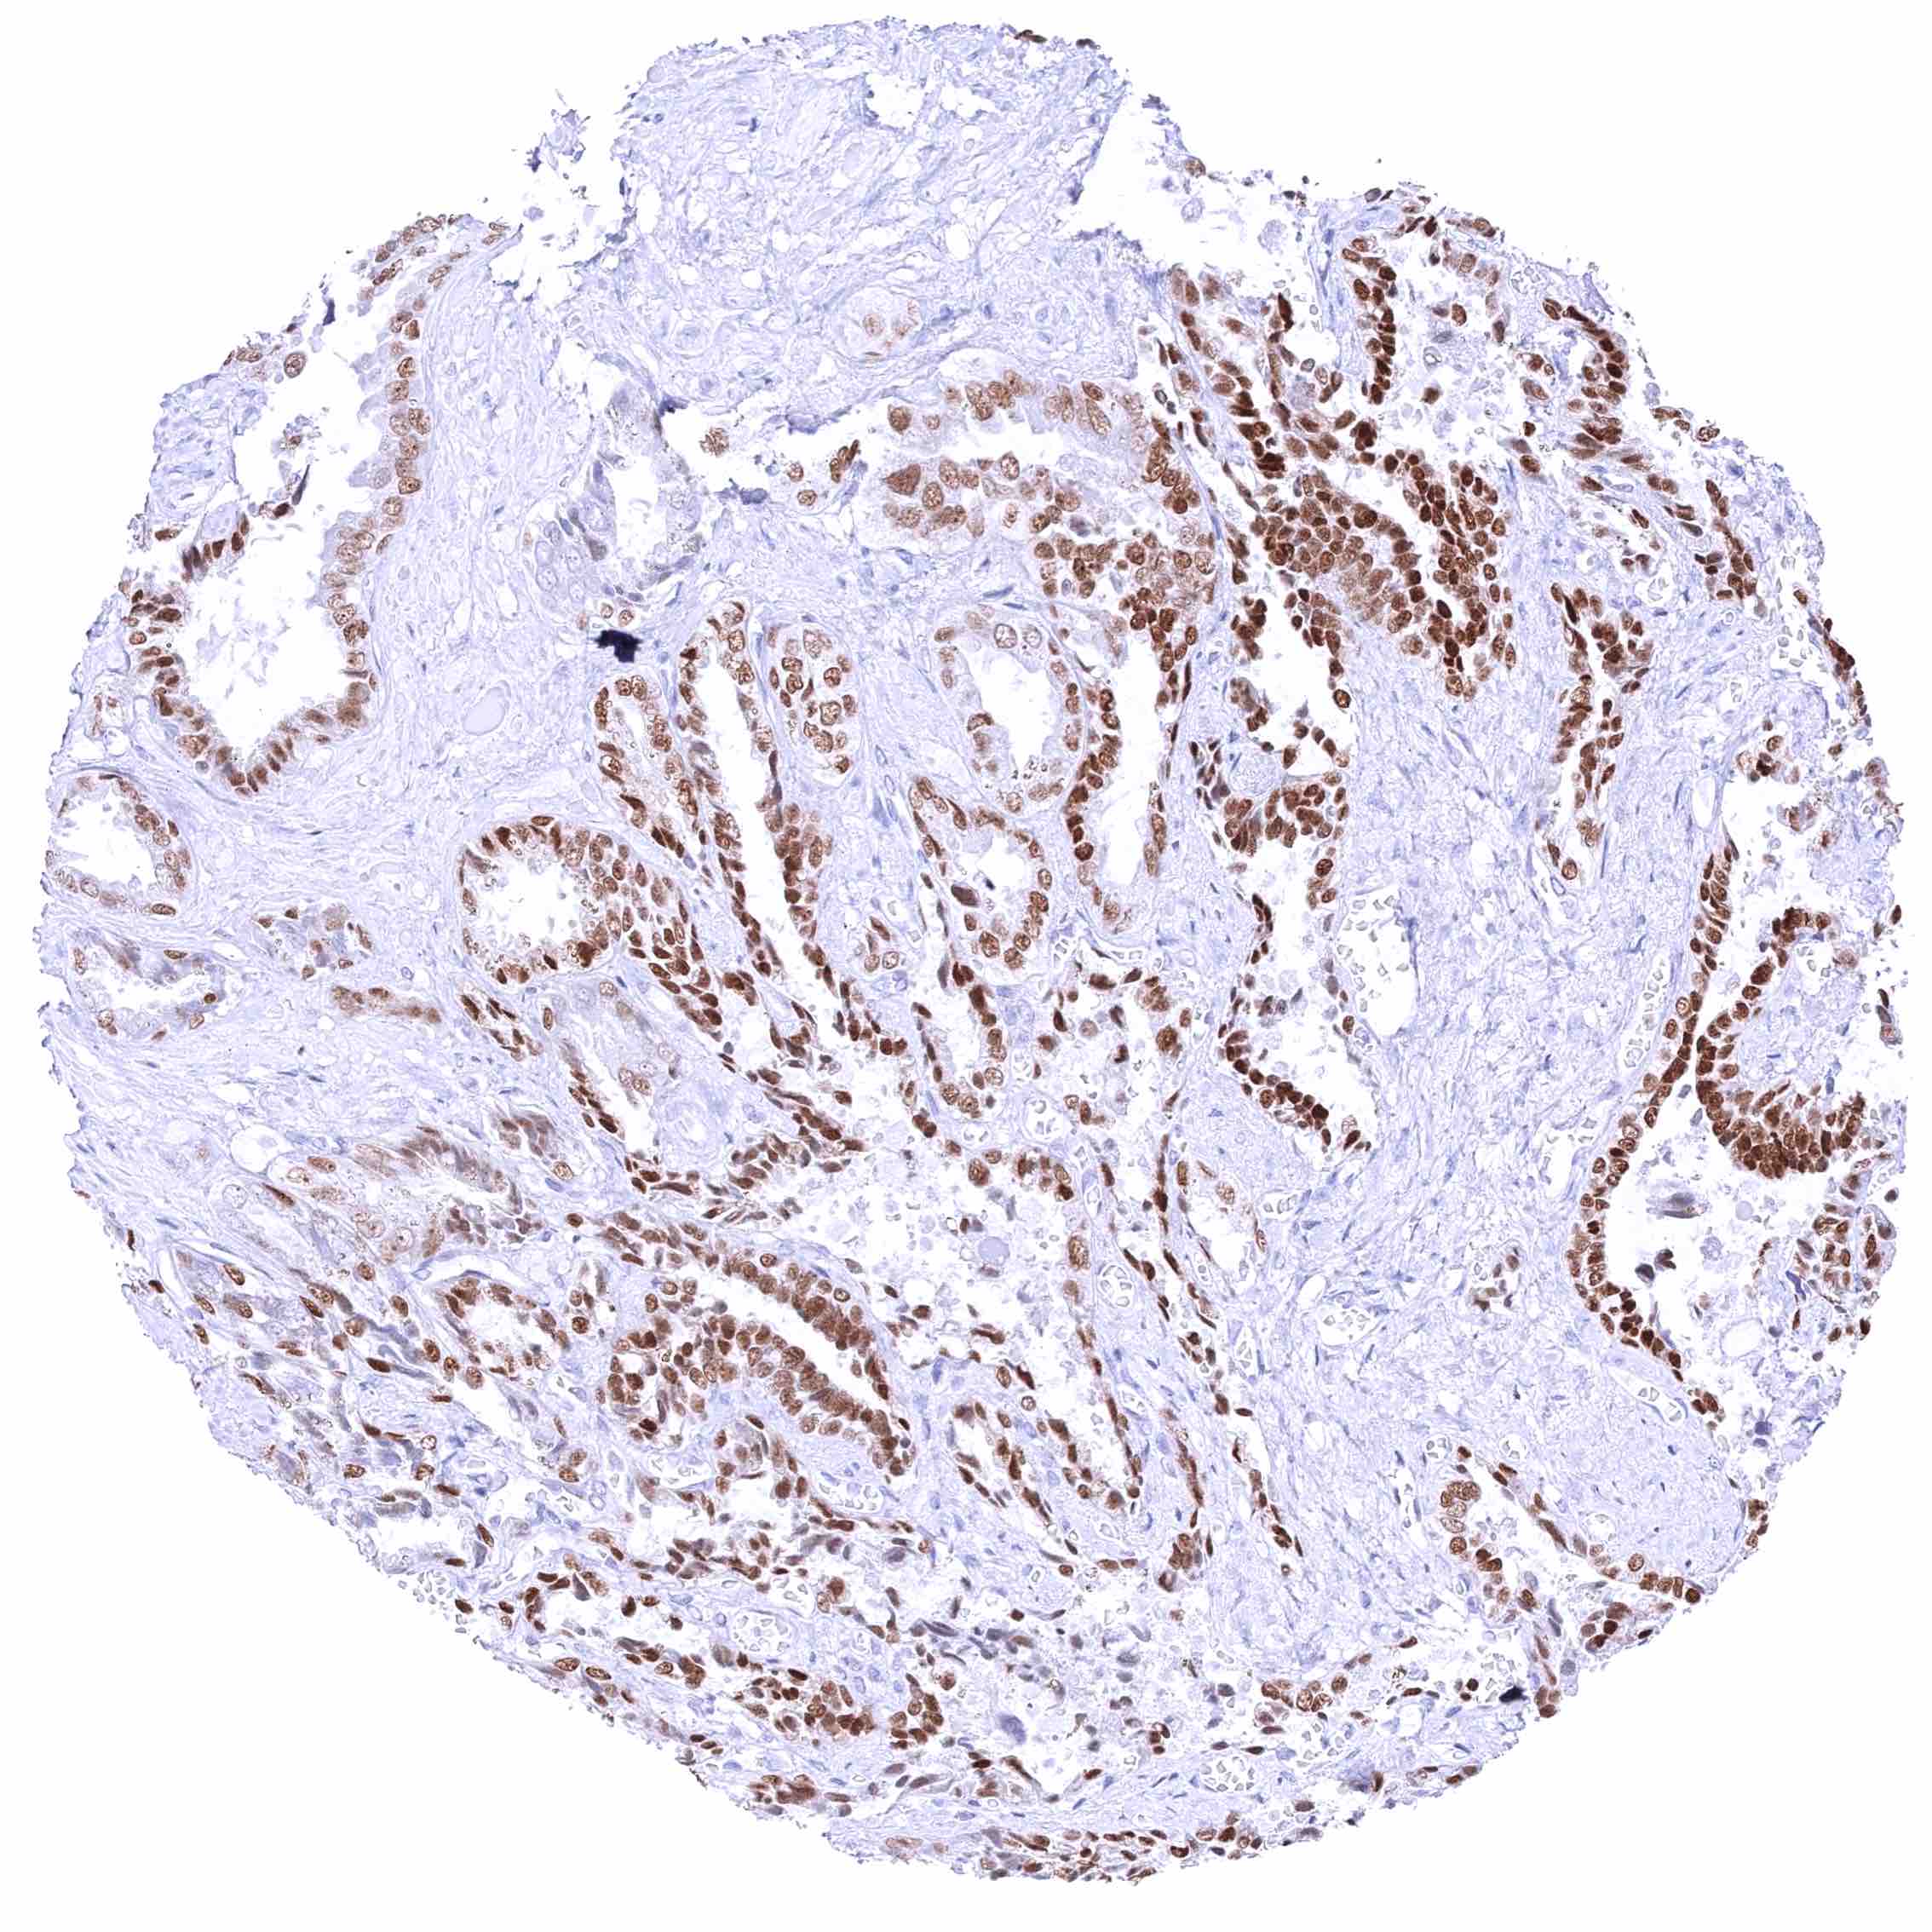

Prostate – Weak to moderate, nuclear GATA3 staining of basal cells. .jpeg